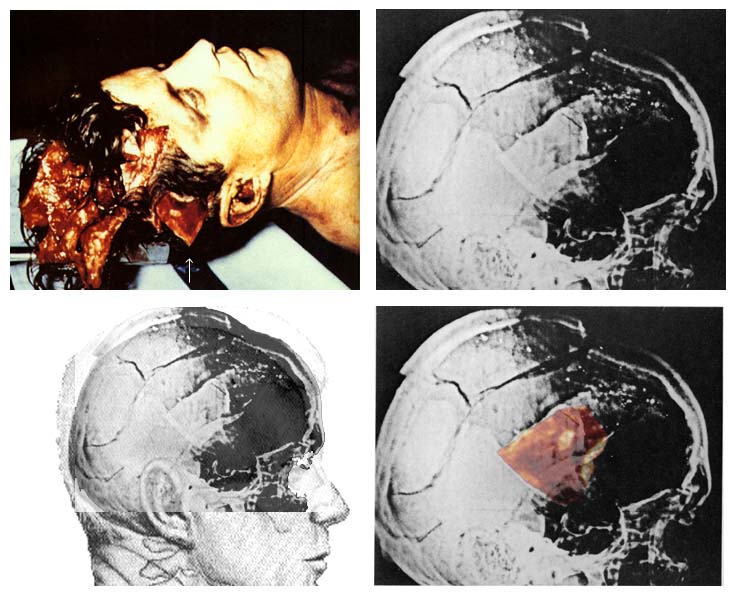

Die Ausrichtung des Schädels! Hier sieht man, wo der "occipital bone" tatsächlich liegt:

So sind die tatsächlichen Verhältnisse

Africanus schrieb:Im Falle der Zeichnung von Ida Dox ergibt sich z.B. das Problem der Perspektive. Die Perspektive in ihrer Zeichnung ist eine andere als die Perspektive in den Röntgenaufnahmen. Es ist deswegen z.B. damit zu rechnen, dass es bei der Anfertigung der Zeichnung zu einem persepktivischen Fehler kommt.

Die Zeichnung von Dox hat bestenfalls eine geringfürgge perspektivische Verzerrung, so unbedeutend, dass sie nicht ins Gewicht fällt